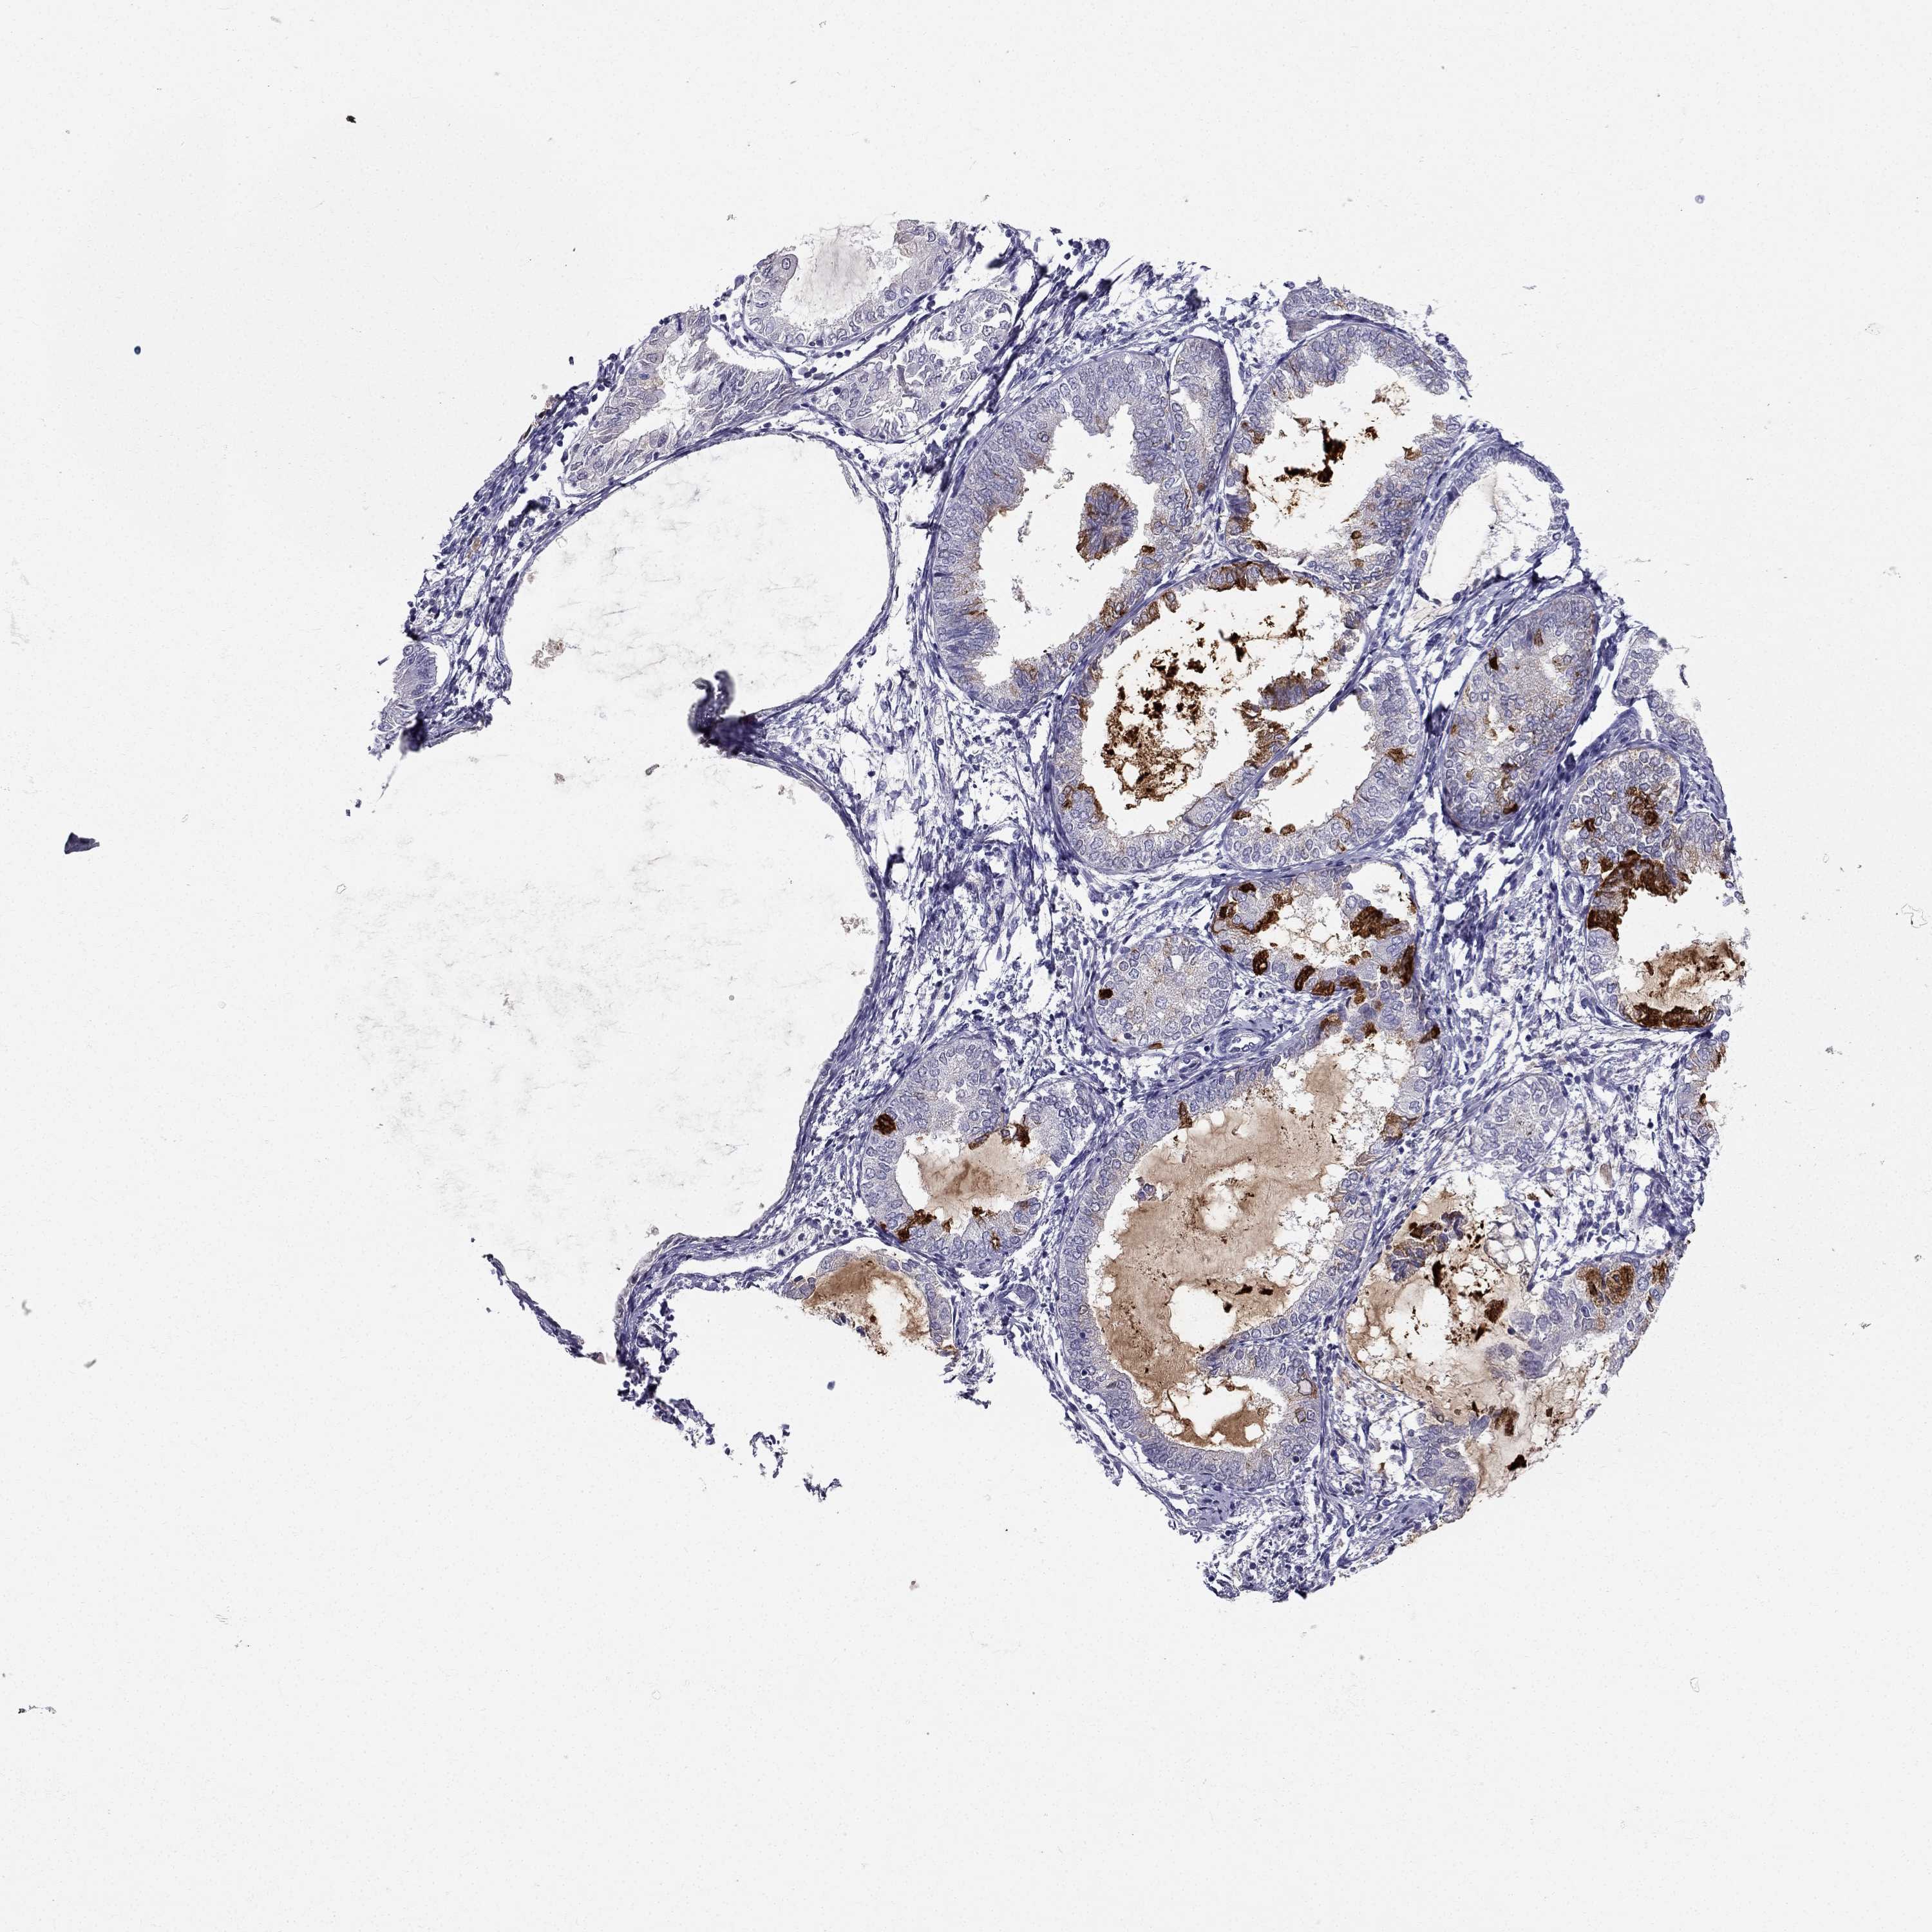

ENDOMETRIAL CANCER - Protein expressioni

A mouse-over function shows sample information and annotation data. Click on an image to view it in a full screen mode. Samples can be filtered based on level of antibody staining by selecting one or several of the following categories: high, medium, low and not detected. The assay and annotation is described here.

Note that samples used for immunohistochemistry by the Human Protein Atlas do not correspond to samples in the TCGA dataset.

Antibody stainingi

Antibody staining in the annotated cell types in the current human tissue is reported as not detected, low, medium, or high, based on conventional immunohistochemistry profiling in selected tissues. This score is based on the combination of the staining intensity and fraction of stained cells.

Each image is clickable and will lead to virtual microscopy that enables deeper exploration of all samples and also displays staining intensity scores, fraction scores and subcellular localization as well as patient and tissue information for each sample.

Antibody HPA035464

Antibody CAB020681

Staining

High

Medium

Low

Not detected

Intensity

Strong

Moderate

Weak

Negative

Quantity

>75%

75%-25%

<25%

None

Location

Nuclear

Cytoplasmic/membranous

Cytoplasmic/membranous,nuclear

Adenocarcinoma, metastatic, NOS